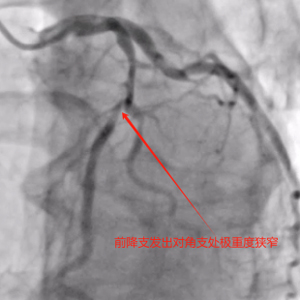

造影可见:前降支中段发出对角支后极重度狭窄,可见侧支循环右冠中远端,回旋支发出钝缘支后闭塞,可见钝缘支侧支循环回旋支远端;右冠中段闭塞。

造影结果比我预想的结果要更差,目前只有一根主血管在维持老吴的生命,情况很棘手,因为近期有过消化道出血情况,术中紧急会诊后,及时与家属沟通,综合评定后再行下一步治疗。手术下台时我给老吴简单的说了一下目前情况,老吴也同意了。